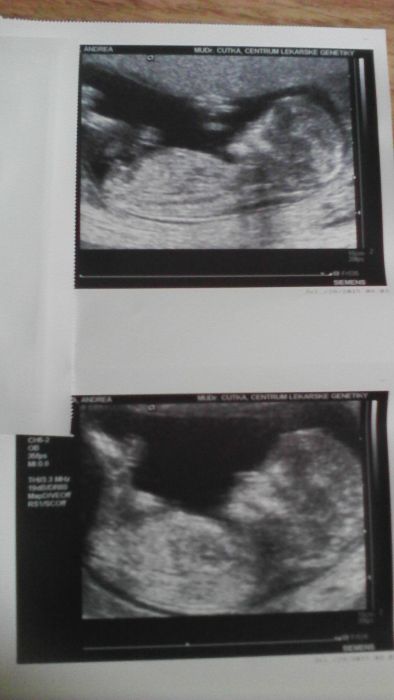

Foťák na tabletu není moc dobrý, ale snad ten Honzík bude alespoň trochu vidět...